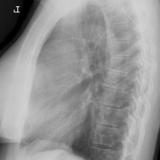

Case 8b Thymoma Lat

Date: 03/27/2009

Views: 14090